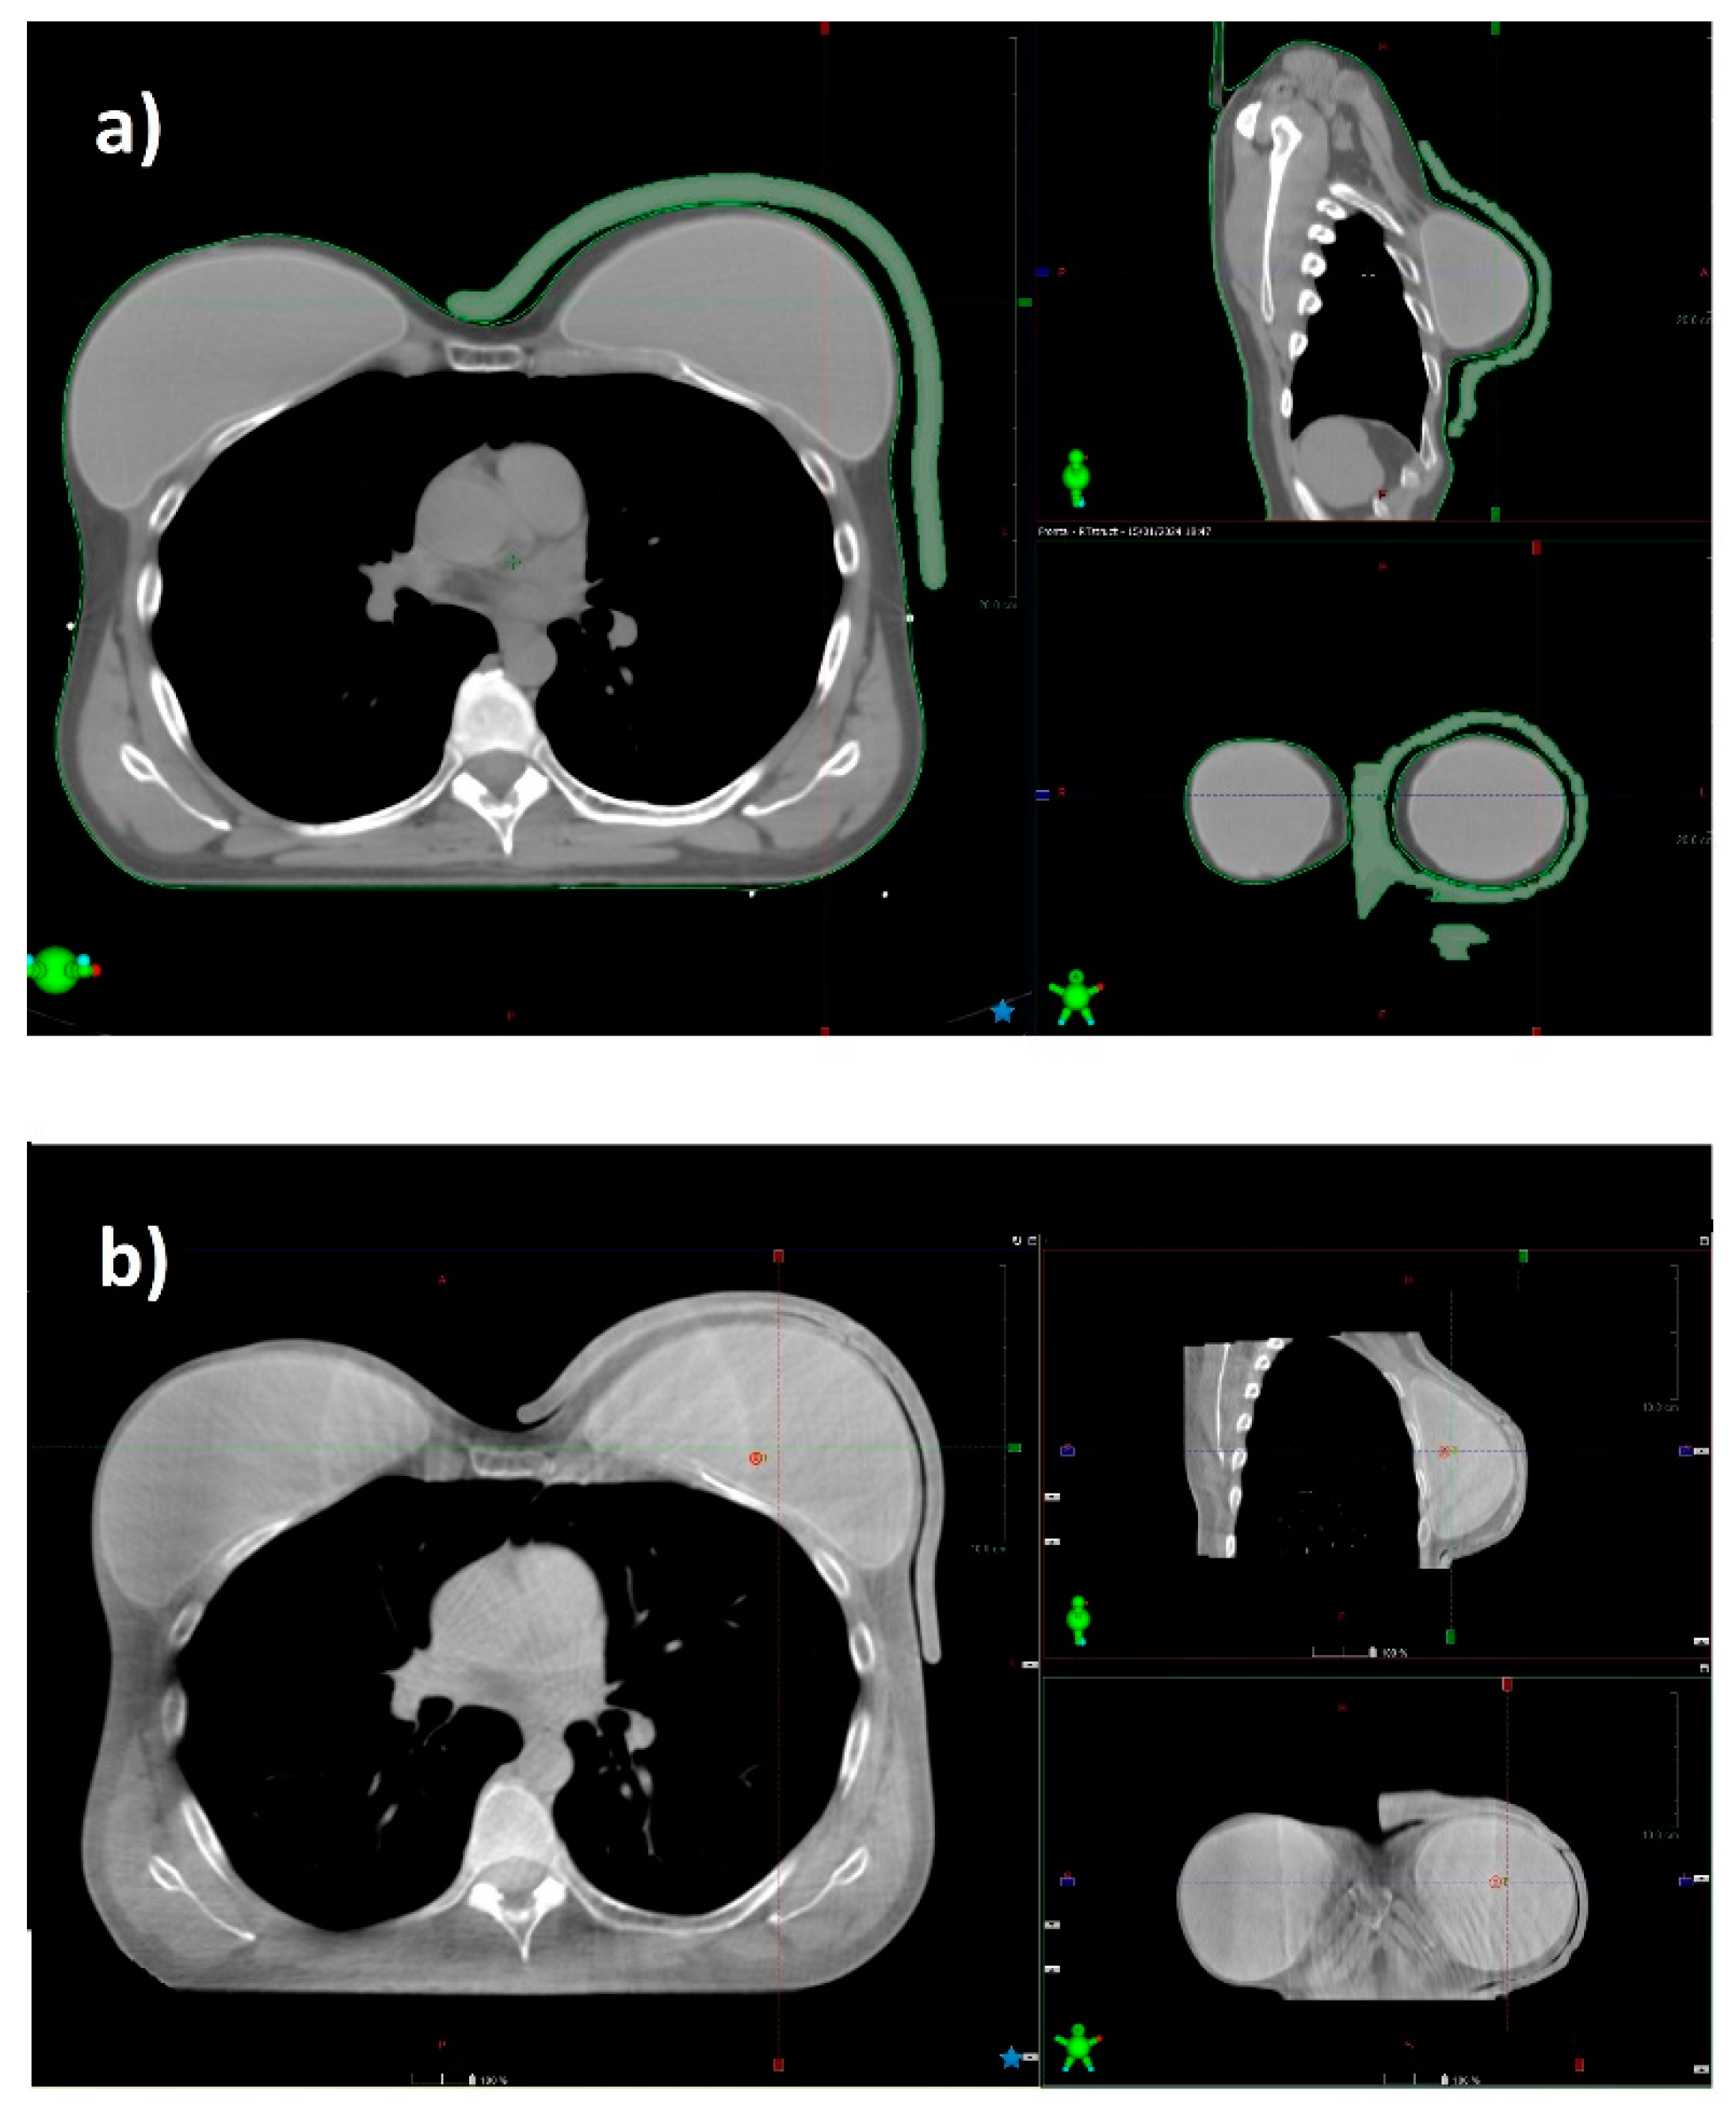

Ensuring adequate contact with the skin using a standard bolus is challenging. Air gaps between the bolus and the skin can lead to an inadequate or inhomogeneous radiation dose delivery to the surface of the skin. At the medial and lateral borders, where the beam axis is more perpendicular to the skin, a relative dose coverage deficit near the skin is critical (Figure 5).

Figure 5. CT scan of a patient with a prosthesis and a standard gel bolus (a), and the CBCT acquired before radiation delivery in the same patient (b). The 3D bolus fits the skin without relevant air gaps.